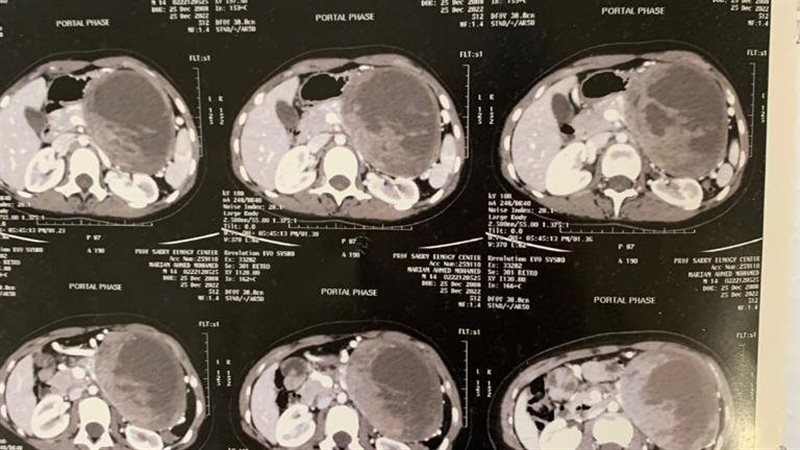

وتلقت العلاج بدون نتيجة وبدون تحسن ملحوظ وقد تم مناظرتها بالعيادة الخارجية بمركز الجهاز الهضمى وأوصى لها بعمل أشعة مقطعية ثلاثية الأبعاد متعددة المراحل ووجد أنها تعانى من ورم كبير بمنطقة البنكرياس..

وقد تشكل فريق للجراحة من الجراحين على مستوى عال برئاسة الدكتور أمجد فؤاد رئيس أقسام الجراحة بكلية الطب وأثناء الجراحة وجد أن الورم 20×24×31 سم وأنه موجود بمنطقة جسم البنكرياس بالكامل وأحاط بشكل كامل بالأوردة والشرايين الخاصة بالطحال وخلف المعدة